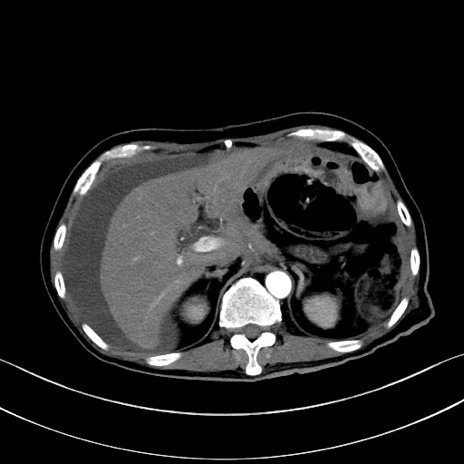

症例28(横断像)

【症例】60歳代男性

【主訴】嘔吐

【現病歴】胃癌にて胃全摘後。食思不振が悪化し、夜中に嘔吐することがある。

【既往歴】胃癌、胃全摘、脾摘、胆摘後

【データ】WBC 5900、CRP 10.56